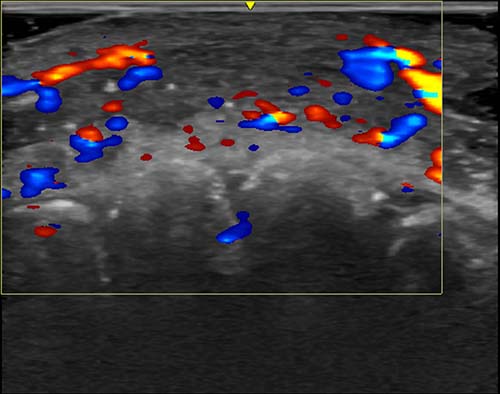

Transgender women who take high levels of estrogen develop breast tissue that appears radiographically similar to the tissue of cisgender women. This includes breast ducts, lobules, and acini, as well as the potential of developing cysts, fibroadenomas, pseudoangiomatous stromal hyperplasia, and other benign findings. In addition, transgender women can have a range of breast densities, and one study found that about 60% have dense or very dense breast tissue.

There is not enough data to determine breast cancer risk for transgender men with top surgery, although some breast cancer cases have been reported, the authors noted. Ultrasound and MRI may be helpful to evaluate transgender men who have a palpable concern but not enough breast tissue for mammography. For transgender men who have not had top surgery, screening and mammography recommendations are the same as for cisgender women.